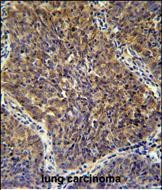

分类: 科研抗体货号: P30879别名: CD2 antigen cytoplasmic tail-binding protein 2, CD2 cytoplasmic domain-binding protein 2, CD2 tail-binding protein 2, U5 snRNP 52K protein, U5-52K, CD2BP2, KIAA1178应用: WB,IHC,FCM反应种属: Human